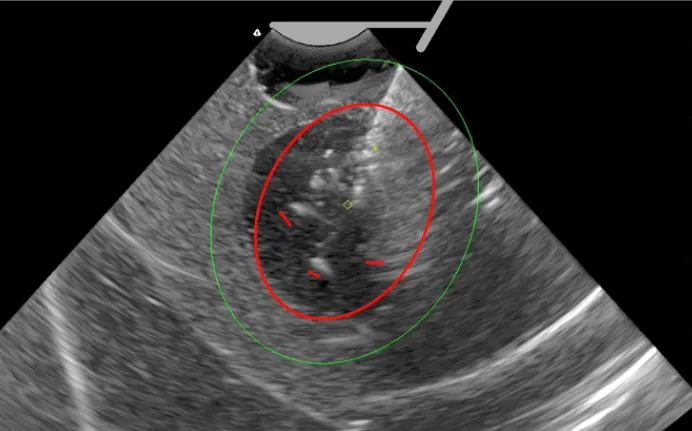

Sonata系统作为一项创新的无切口、无扩张的经宫颈消融技术,其核心在于利用射频(RF)能量精准消融子宫肌瘤组织。该系统由图像引导软件(GGS)、射频能量发生器、子宫内超声探头以及射频消融电极等关键组件构成,各部件协同工作,确保了治疗过程的高效与安全。

图像引导软件(GGS)集成了子宫肌瘤的定位、消融计划制定与实时监控功能,其智能引导特性能够在超声图像上直观展示消融区域与热安全边界的图形叠加,从而帮助医生精确选择消融目标,优化部署位置,有效避免正常组织受到过高温度的损伤。子宫内超声探头则负责精准定位子宫肌瘤的位置,为后续消融操作提供精确指导。

射频能量发生器作为系统的动力源泉,为消融电极提供稳定、精准的射频能量输出,实现了快速、安全的消融效果。而射频消融电极则扮演着控制SMART Guide并设置消融区域的关键角色,它与子宫内超声探头紧密相连,共同实现了超声引导下的射频消融治疗。